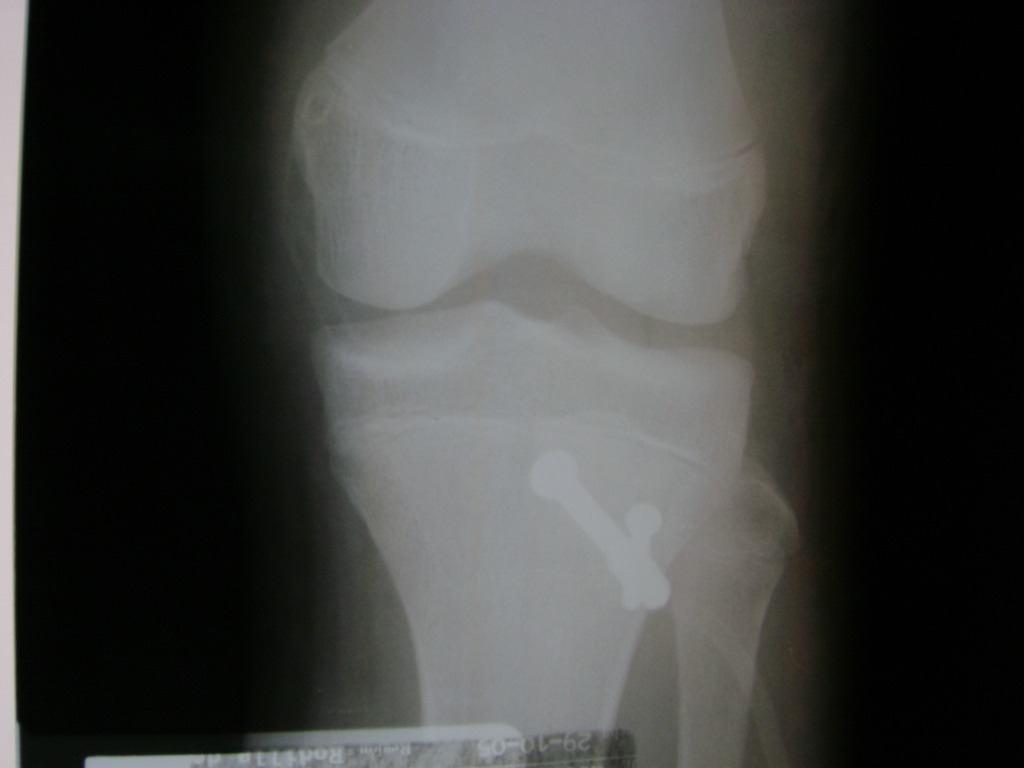

La artroscopia de rodilla es un cirugía en el cual la estructura interna de la articulación es examinada ya sea para realizar un diagnostico o para realizar un tratamiento, este procedimiento se realiza utilizando un instrumento parecido a un pequeño tubo llamado artroscopio.

La artroscopia se popularizo en 1960 y hoy en día es muy común en todo el mundo. Típicamente, es realizada por cirujanos ortopédicos de manera ambulatoria. Cuando se realiza de manera ambulatoria los pacientes pueden regresar a casa después de la operación, no se requiere quedarse en hospital.